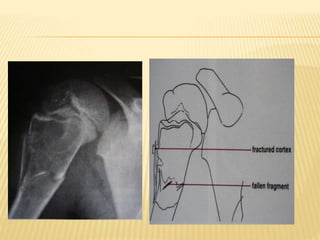

SIMPLE BONE CYST(UNICAMERAL CYST)

 Developmental anomaly of physis

 Etiology: Unknown –transient failure of ossification

of physeal cartilage & cyst formation

 C/F: 9-13 yrs, 2:1 male predominance. Silent until

pathological fracture occurs.

 Location:75% - humerus and proximal femur.

 Xray – well marginated,central lytic lesion

Fallen-leaf or Fallen-fragment sign

SBC of humerus(truncated cone appearance)

SBC with pathological fracture